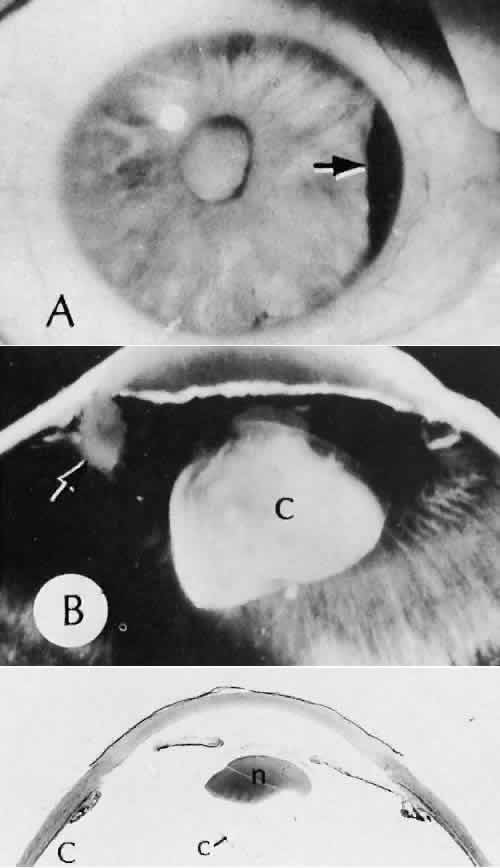

Epithelial downgrowth (ingrowth) (Fig. 44) is one of the most serious causes of pseudophakic glaucoma, in which surface epithelium (probably from the conjunctiva) grows into the anterior chamber. This condition is more likely to occur with fornix-based conjunctival flaps than with limbus-based flaps and in eyes with problems in wound closure, such as vitreous loss, wound incarceration of tissue, delayed reformation of the anterior chamber, or frank rupture of the limbal incision, and when instruments such as iridectomy forceps are contaminated with surface epithelium before they are introduced into the eye. Epithelial downgrowth causes an anterior chamber angle closure by means of peripheral anterior synechiae or lines an open anterior chamber angle and obstructs aqueous outflow mechanically. Histologically, the epithelium is seen to grow most luxuriously and in multiple layers on the iris where there is a good blood supply, but it tends to grow sparsely and in a single layer on the posterior surface of the avascular cornea. The epithelium may extend behind the iris, over the ciliary body, and even far into the interior of the eye.

Fig. 44. A case of epithelial downgrowth. A. The clinical findings are subtle and consist of a translucentmembrane on the posterior corneal surface, often contiguous with an ocular wound, characterized by a well-defined, linear leading edge. In this case, the leading edge is just above the corneal light reflex. B. In contrast, in this case, the leading edge is just below the corneal light reflex. The surgical procedure in both cases appears to have been complicated because of the presence of sector iridectomies. C. In this case, surface stratified squamous epithelium lines the posterior cornea (including the posterior aspect of the clear corneal wound) and extends over delicate trabecular tissue onto the anterior surface of the iris. The epithelium will adapt the tissue over which it grows to produce an adhesive surface appropriate to its attachment requirements. This adaptive process that is an advantage for the epithelium will permanently destroy the function of the trabecular meshwork over which the surface epithelium extends. D. The actual site of the fistula allowing the epithelium to gain access to the internal surfaces of the eye is rarely found on histologic sections. Higher magnification of the area of the wound, however, does show the presence of foreign material in the incision. Polarized material (inset) consistent with degenerating silk suture is present. Invasion of the epithelium along a suture tract is one possible route of entrance. (Hematoxylin-eosin stain with and without polarization; A, × 21; B, × 101)